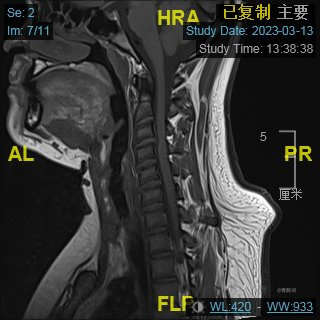

颈部磁共振平扫: